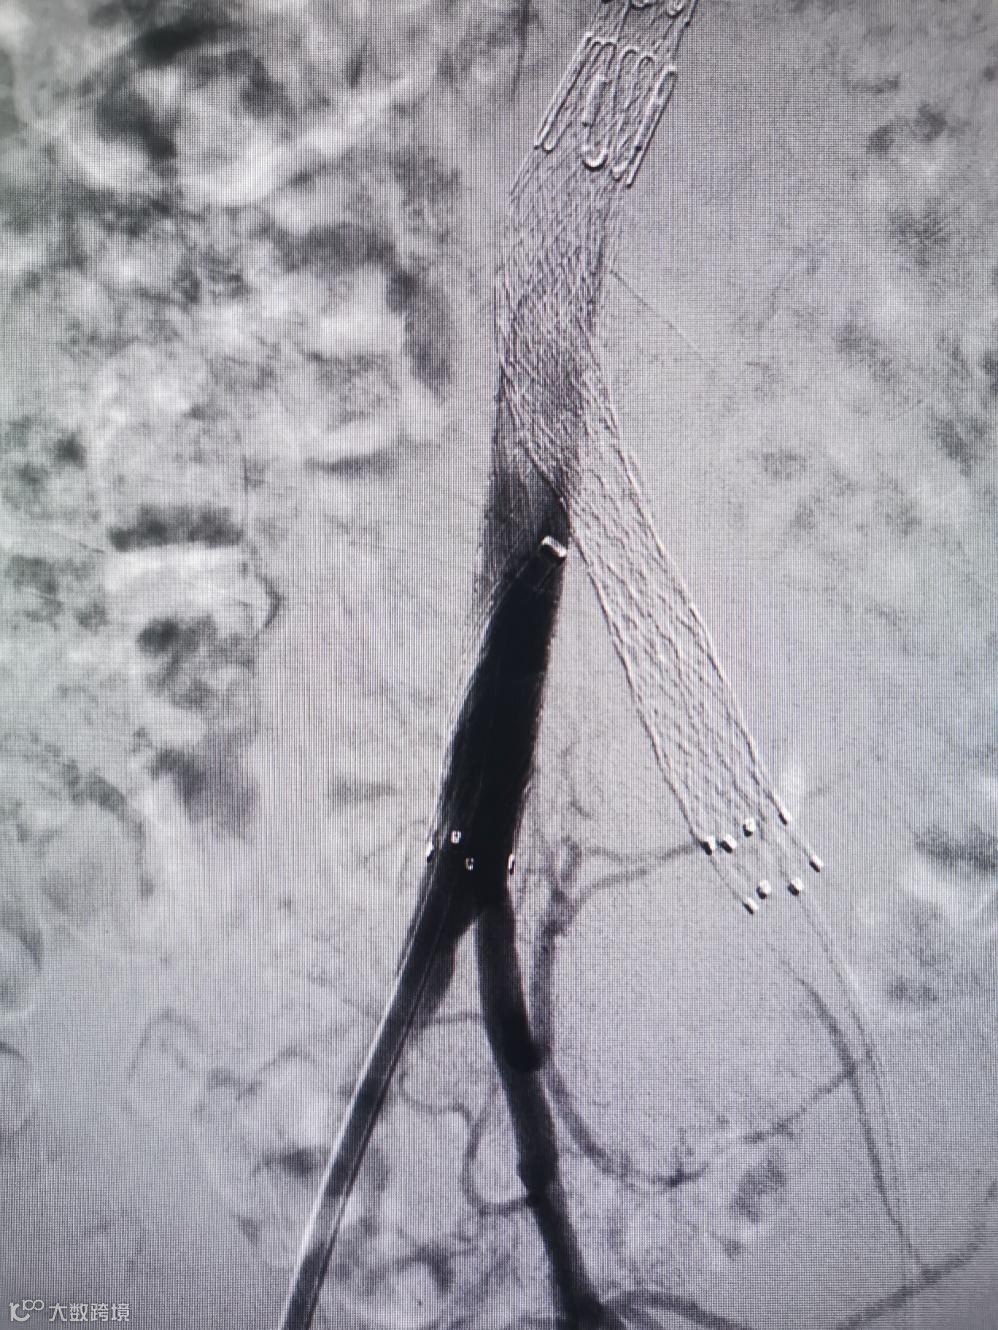

Separator With Aspiration catheter for Mechanical Thrombectomy(MT)【分离器辅助导管抽吸技术】:旨在提高整体系统的抽吸效率和治疗安全性,快速帮助血栓清除。

1)抽吸导管头端堵管,分离器可以快速疏通导管,降低撤管冲洗的频率。

2)针对大负荷血栓或亚急性血栓,分离器辅助下抽吸能提升整体系统抽吸效率,缩短手术时间。